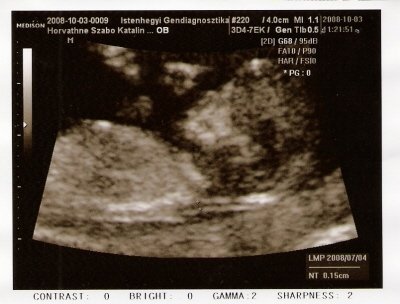

és szombat óta én is érzem a piciketesót, majdnem elbőgtem magam meghatottságomban, vezetés közben éreztem először, de rossz, hogy még nem mindig

mert többnyire nincs időm figyelni. Már várom, hogy jól rugdosson oldalba, ha nem figyelek rá eléggé

ez a legjobb az egész babavárásban

és én úgy emlékszem, hogy elképzelni sem tudtam, milyen lehet, de azonnal tudtam,mikor réka először megmozdult, hogy ez az! ez a 20. héten volt...

Pocakom is van, kb 25 hetesnek megfelelő... de gondolom ez azért mert jól egymás után jöttek a csemeték,én meg jól kihagytam a hasizom-gyakorlatokat a porckorongsérvemre hivatkozva

tünemény, van egy emlékkképem, hogy a 16. héttől hall a magzatka. Nem tuti, de mintha. SZóval hajrá zenehallgatás! Én örülök ha csend van körülöttem